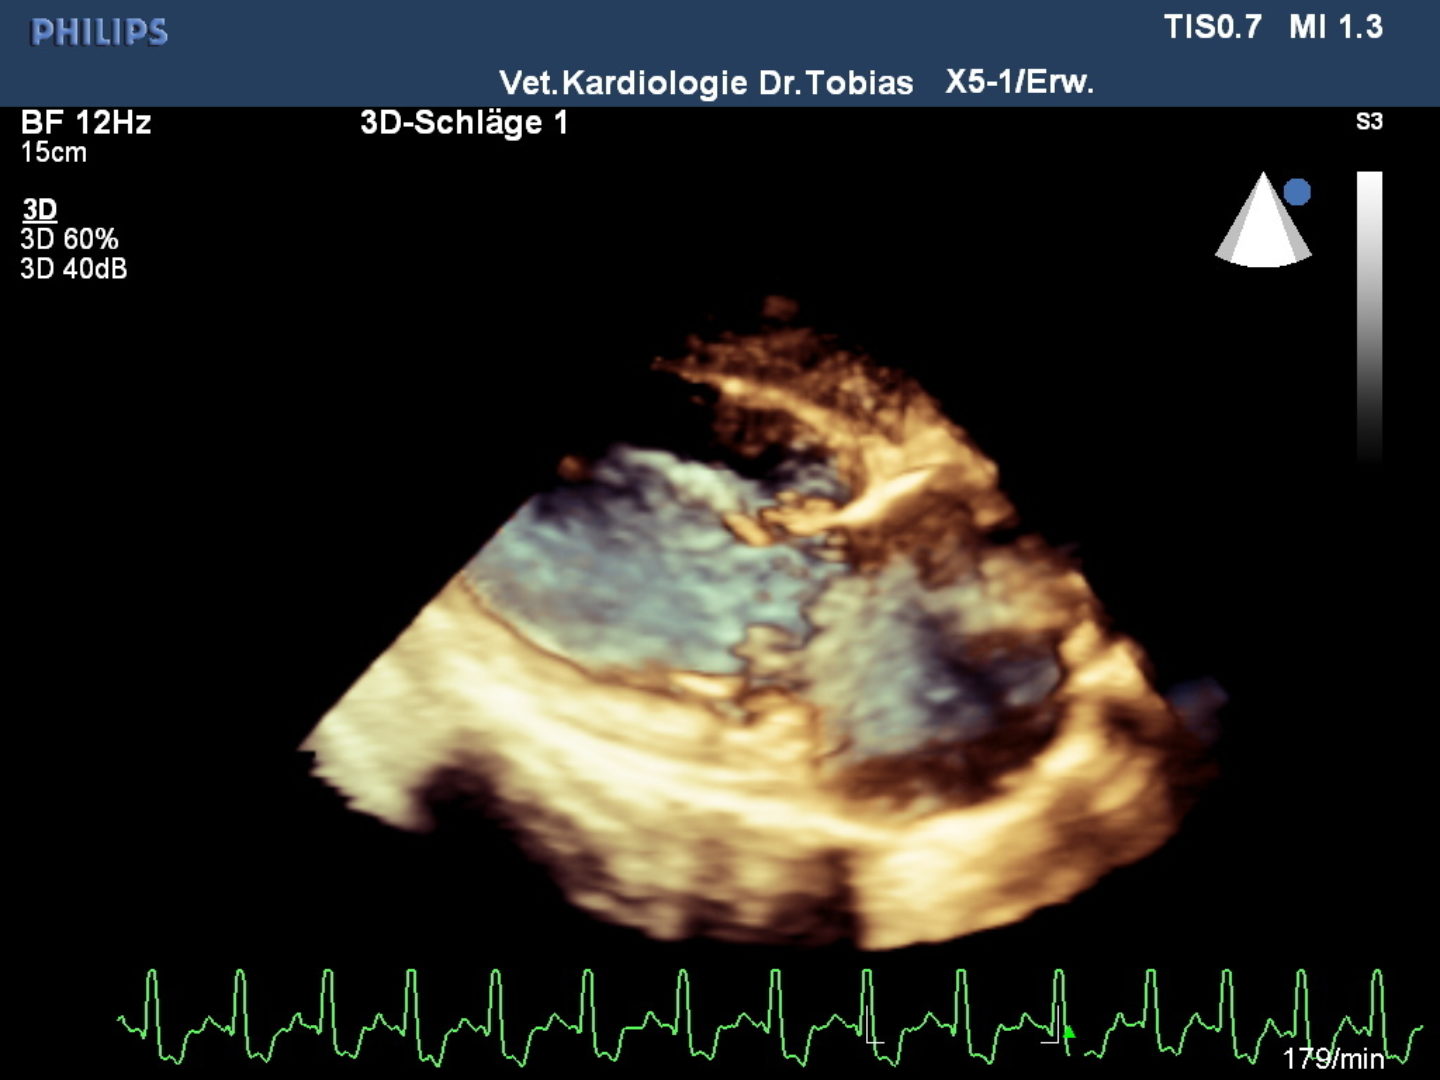

Neben der Auskultation und dem Röntgen stehen dem Veterinärkardiologen die gleichen Untersuchungsmethoden zur Verfügung, wie sie auch in der Humanmedizin Anwendung finden: das Elektrokardiogramm erlaubt eine Rhythmus und Frequenzanalyse, die Blutdruckmessung ist ungleich schwieriger als in der Humanmedizin und spielt bei Katzen eine größere Rolle als beim Hund, das Fundament der Kardiologie ist die Herzultraschalluntersuchung, die den Sitz und die Charakterisierung der Krankheit erlaubt sowie eine Schweregradbestimmung. Zur anatomischen Darstellung werden ein- und zweidimensionale Methoden genutzt, auch 3D- und 4D–Methoden sind in spezialisierten Einrichtungen zu finden. Die Blutflussdarstellung erfolgt mit verschiedenen Dopplermethoden, die viele Hundebesitzerinnen auch aus Schwangerschaftsuntersuchungen kennen. Neuere Methoden zur Herzmuskeluntersuchung sind die Speckle Tracking- und Gewebedopplermethoden.

Rike wurde einer modernen Echokardiographieuntersuchung nach nationalem und internationalem Standard unterzogen und zusätzlich eine 3D/4D-Bildbetrachtung vorgenommen und ihre Herzmuskelleistung via Speckle Tracking untersucht. Die Untersuchung bestätigte eine offene Verbindung zwischen Aorta und Pulmonalrterie, die sich bei der Geburt hätte schließen müssen. Durch die Volumen und Drucküberladung kommt es zu einer Linksherzbelastung, die zu einer deutlichen Vergrößerung der linken Kammer geführt hat. Infolge der Kammervergrößerung wird die linke Vorkammer-Kammerklappe undicht und zunehmend Blut in Richtung Lunge zurücklassen, was das Stauungsrisiko weiter steigert. Typischerweise erhöht sich wie auch bei Rike der Aortendruck, ohne dass anatomische Anzeichen einer Stenose festzustellen wären. In der Pulmonalarterie ist im Farbdoppler ein chaotisch-turbulentes Signal zu sehen, während die Ductusampulle laminar bleibt. Im EKG zeigten sich bereits verlängerte Überleitungszeiten im Kammerkomplex QRS und Senkung des ST-Segmentes, als Zeichen einer Hypoxie des Herzmuskels.